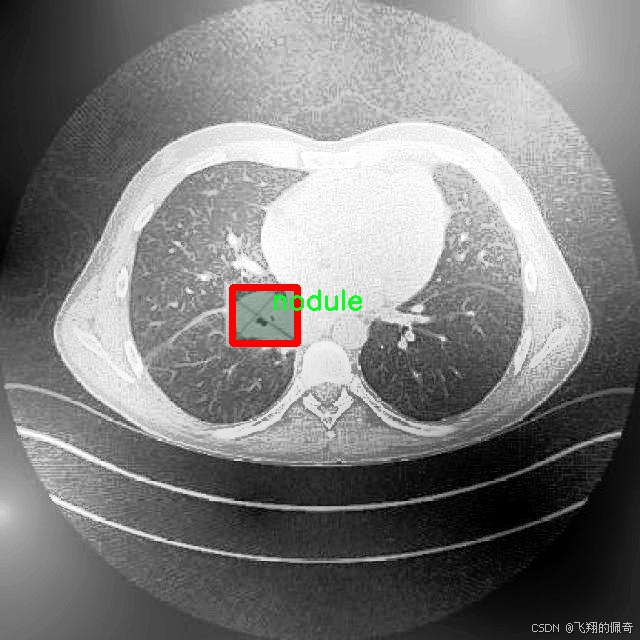

本研究将基于改进的YOLOv8模型,构建一个高效的肺结节图像分割系统。所使用的数据集包含1600幅图像,涵盖了三类重要的病理类型:腺癌、癌症和结节。这些数据不仅为模型的训练提供了丰富的样本,也为后续的模型评估和验证奠定了基础。通过对不同类别的肺结节进行精确分割,研究旨在提高模型在实际应用中的鲁棒性和准确性,进而为临床医生提供更为可靠的辅助诊断工具。

图片效果

在肺结节图像分割的研究中,数据集的选择与构建至关重要。本研究所采用的数据集名为“Lung Nodule Segmentation study”,其设计旨在为改进YOLOv8-seg模型提供高质量的训练数据。该数据集专注于肺部影像中的结节分割,特别是针对不同类型的肺结节进行精确标注,以便于后续的深度学习模型训练和性能评估。

“Lung Nodule Segmentation study”数据集中包含三种主要类别,分别为腺癌(adenocarcinoma)、癌症(cancer)和结节(nodule)。这些类别的选择不仅反映了肺部影像学中的常见病理类型,也为模型的多样性和适应性提供了基础。腺癌作为一种常见的肺癌类型,其在影像学上的表现与其他类型的肺结节有显著差异,因此在数据集中占据了重要地位。癌症这一类别则涵盖了更广泛的病理变化,旨在提高模型对不同癌症类型的识别能力。结节类别则是数据集的核心,主要用于训练模型在图像中准确识别和分割出肺结节的区域。